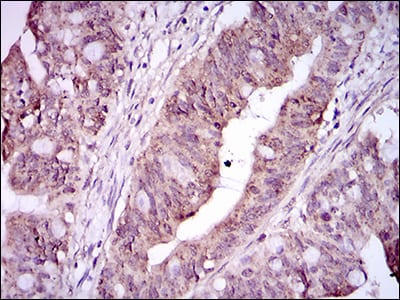

分类: 科研抗体货号: 30486P别名: ERBB; HER1; mENA; ERBB1; PIG61应用: WB,IHC,FCM反应种属: Human

分类: 科研抗体货号: 30486A别名: ERBB; HER1; mENA; ERBB1; PIG61应用: WB,IHC,FCM反应种属: Human